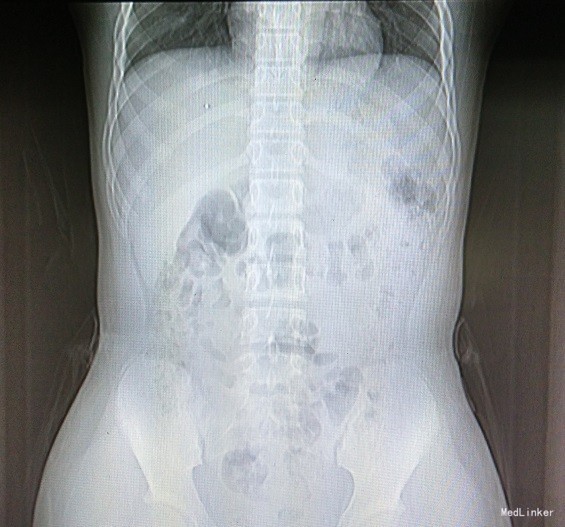

主诉:女,10岁,确诊“1.左侧卵巢无性细胞瘤(Ⅳ期)2.右侧卵巢混合型生殖细胞瘤(无性细胞瘤,绒癌,畸胎瘤)(Ⅳ期)”2+月,拟化疗 病史:患儿于2+月前“因撞击后间断腹痛27天”就诊于当地医院,腹部B超示:盆腔查见大小约7.3*5.4*5.2cm类圆形中等回声团,另于右腹部查见大小约11.6*14.0*12.6cm类圆形中等回声团。1+月前来我院查肿瘤标志物:AFP19.6ng/ml,ThCG33076mIU/ml, CA125:235 U/ml。于我院小儿外科行手术,术后病检为:左侧卵巢无性细胞瘤,右侧卵巢混合型生殖细胞瘤(无性细胞瘤约70%,绒癌约20%,畸胎瘤约10%),术后在我科规律化疗,予以依托泊苷+顺铂+平阳霉素+环磷酰胺化疗,过程顺利,为继续化疗遂入院治疗。

查体:慢性病容,面色及口唇苍白,口腔黏膜略苍白,右侧腹可见约10cm陈旧性手术疤痕。 辅检:血常规:WBC 1.7×109/L 、N:1.01×109/L,Hb75g/L,PLT30*10^9/L,